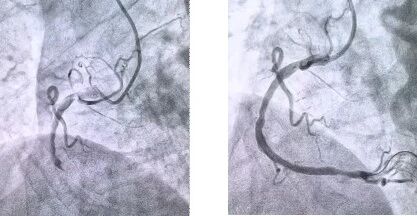

患者抵達醫(yī)院后,簡化掛號、繳費等中間環(huán)節(jié),迅速溝通病情,需要緊急介入治療,獲得家屬同意,立即送至導管室。造影顯示其右冠狀動脈中段完全閉塞,醫(yī)生迅速實施血栓抽吸,球囊擴張和藥物洗脫支架植入術。36 分鐘后,閉塞血管恢復正常血流,吳大爺?shù)难獕?、心率逐漸平穩(wěn),胸痛癥狀明顯緩解。術后三天,他便轉(zhuǎn)入普通病房進行康復訓練,重拾健康生活。